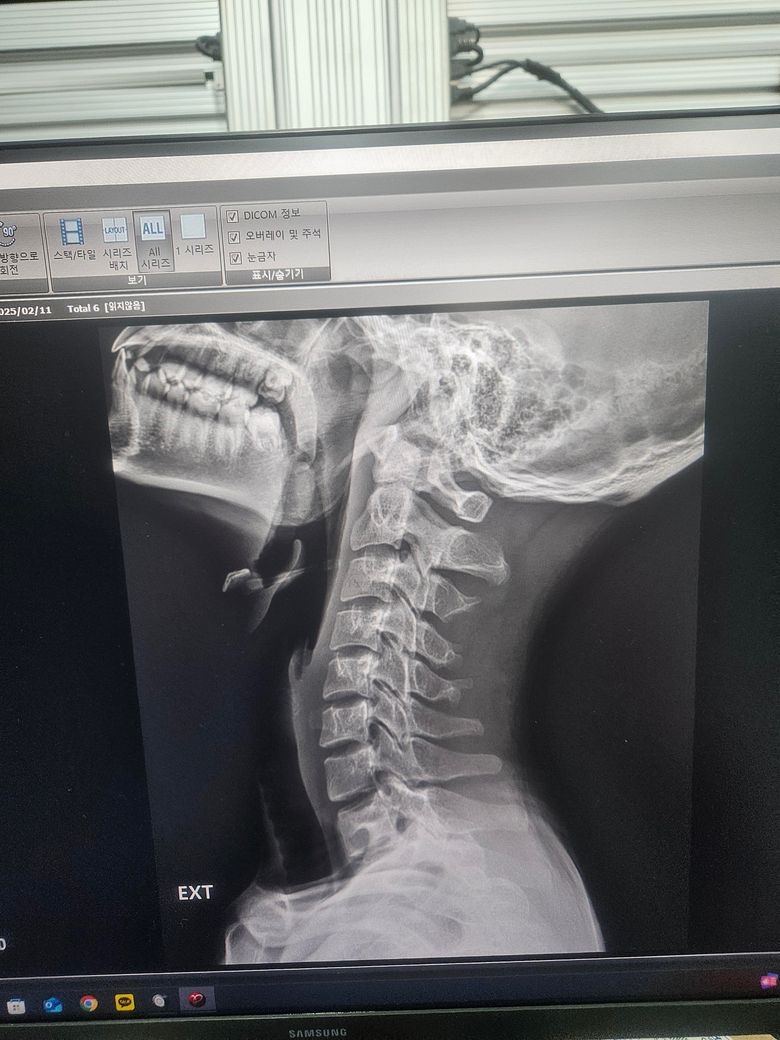

경추 불안정증인가요? 자세히 봐주세요 경추 1번 2번

경추 1번 2번 굴곡 신전시 이상이 있나요 제가 볼땐 많이 떨어지는것 같은데 다 아니라고 하시네요 전문의 답변 기다립니다 부탁드려요

• 1번 째 사진

올려주신 엑스레이 사진에서 특별한 이상 소견은 저명하지 않습니다.